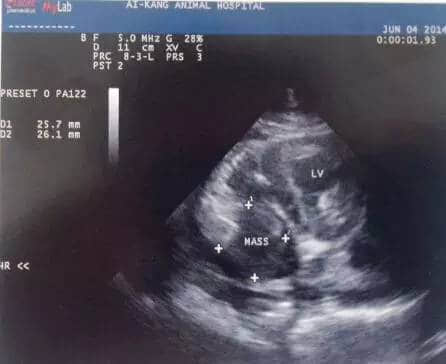

超声心动图检查是心脏肿瘤诊断最敏感的工具(图5、6),用于确定心脏肿物存在和心包积液的发生,心脏腔室的大小、形状和心室功能的继发性改变也可检查出。在二维超声心动图中,心包积液的存在有利于确认进入心包腔的心基部肿瘤,同时良好的对比度也对心腔内部的肿物有较好的显现作用。此外,多普勒超声心动图可评估相关的血流异常,确定肿物对血液回流心脏及心输出量的影响。

图5. 4岁柯基犬超声心动图,右心房内可见2.5x 65px不均质回声肿物。